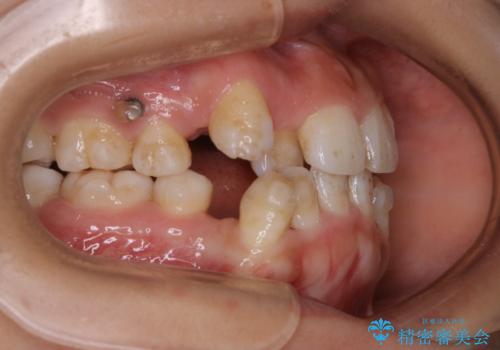

- インビザライン中に、コーヒーによる着色が気になるとのことでした。PMTC60分コースを行いました。

PMTC(保険外治療)は、毎日の歯磨きで落としきれない汚れや、コーヒ、紅茶・タバコのヤニなどの着色も除去します。目には見えない歯と歯の間・歯肉の境目・インビザライン中はアタッチメント周囲などに残っているプラーク(歯垢)もしっかり取り除きます。PMTCでは専門的な機械や材料を使用して、徹底的に汚れを除去するため、虫歯・歯周病・口臭予防などにつながります。